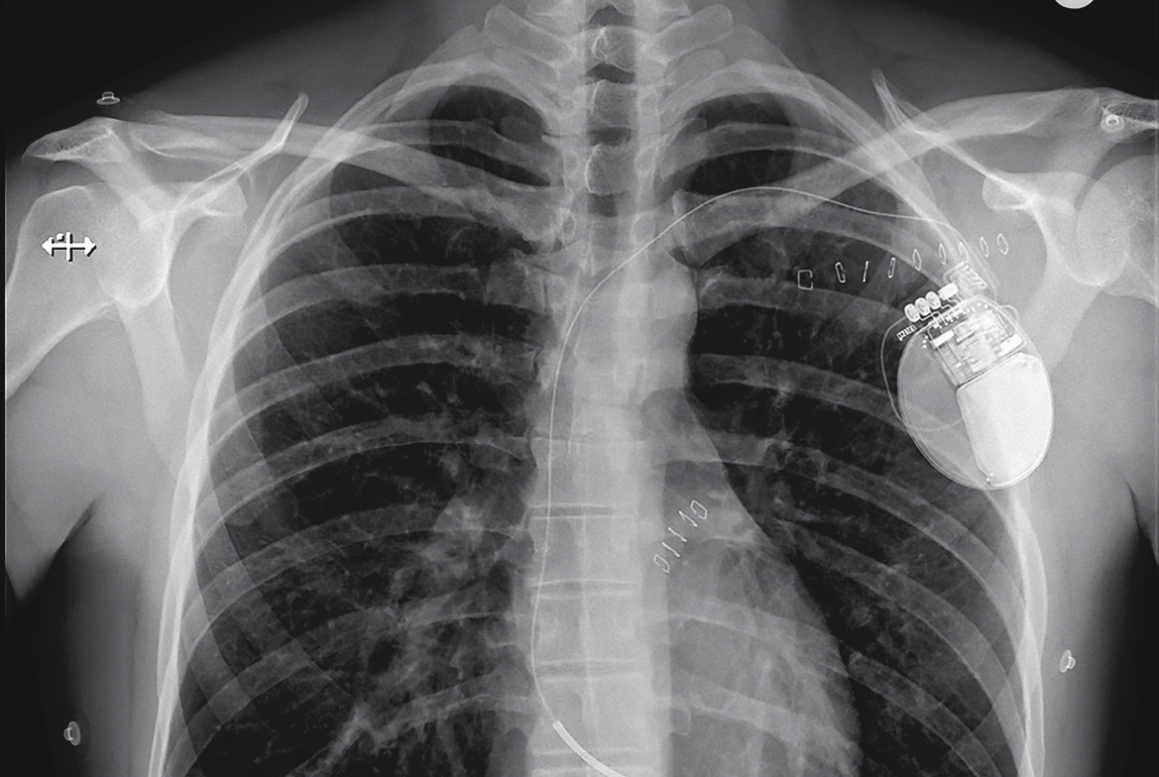

ICD steht kurz für Implantable Cardioverter-Defibrillator. Es handelt sich dabei um jenes Gerät, das aufgrund des dänischen Fußballspielers Christian Eriksen durch die Medien ging. Auch Eriksen ist mit seinen 29 Jahren sehr jung, als er das Gerät in seine Brust als Reaktion auf Herzversagen implantiert bekommt. Das Gerät verfüge über zwei Funktionen, erklärt Daniel Reifecker. Während die Herzschrittmacherfunktion Herzrasen durch kleine Stromimpulse unterbrechen und das Herz in einen normalen Sinusrhythmus zurückbefördern kann, kommt die Defibrillatorfunktion erst im äußersten Notfall mit massiven Stromschlägen zum Zuge. Die Herzschrittmacherfunktion sei etwas unangenehm, aber nicht schmerzhaft, erzählt Reifecker. „Ich merke sie besonders in der Nacht, weil bei mir, wenn ich schlafe, manche Herzschläge ausbleiben. Ich wache dann auf." Das passiere etwa ein bis zwei Mal pro Woche.

ICD - implantierbarer Defibrillator

Beim Risiko eines lebensbedrohlich zu schnellen Herzschlags kommt ein implantierbarer Defibrillator, auch ICD genannt, zum Einsatz. Betroffen sind vor allem Patienten mit erheblicher Herzschwäche. Ähnlich wie Herzschrittmacher stimulieren ICD-Geräte die rechte Seite des Herzes, wobei es Ein- und Zweikammerversionen gibt. Zusätzlich wird der Herzrhythmus ständig überwacht. Sobald das Gerät eine Beschleunigung bemerkt, die ihren Ursprung in der Herzkammer hat, gibt es regulierende Impulse ab. Reichen die nicht aus, um den Rhythmus zu normalisieren, erfolgt ein Defibrillationsschock, um die Störung beseitigen.